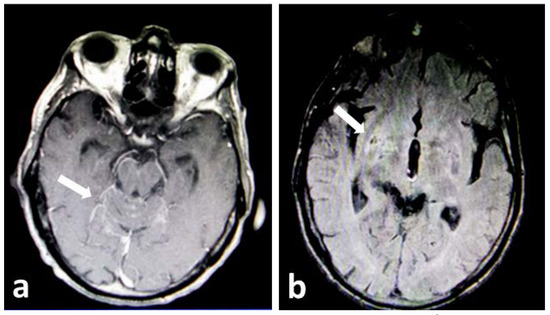

Fulminant Cryptococcal Meningoencephalitis After Successful Treatment of Primary Cutaneous Cryptococcosis

Introduction: Cryptococcal meningoencephalitis is a life-threatening disease affecting mainly immunocompromised hosts. Case report: We present a case of a 64-year-old immunocompetent patient, who initially developed a traumatic scalp skin infection due to Cryptococcus neoformans. The patient received oral fluconazole and subsequently liposomal [...] Read more.

Introduction: Cryptococcal meningoencephalitis is a life-threatening disease affecting mainly immunocompromised hosts. Case report: We present a case of a 64-year-old immunocompetent patient, who initially developed a traumatic scalp skin infection due to Cryptococcus neoformans. The patient received oral fluconazole and subsequently liposomal amphotericin B due to the development of resistance with resolution of the infection. Two years later, during chemotherapy for newly diagnosed gastric and lung cancer, he developed fulminant cryptococcal meningoencephalitis, which did not respond to liposomal amphotericin B and flucytosine. Conclusions: To our knowledge, this is the first case of fulminant cryptococcal meningoencephalitis following long latency after adequately treated primary cutaneous infection. Full article

Figure 1